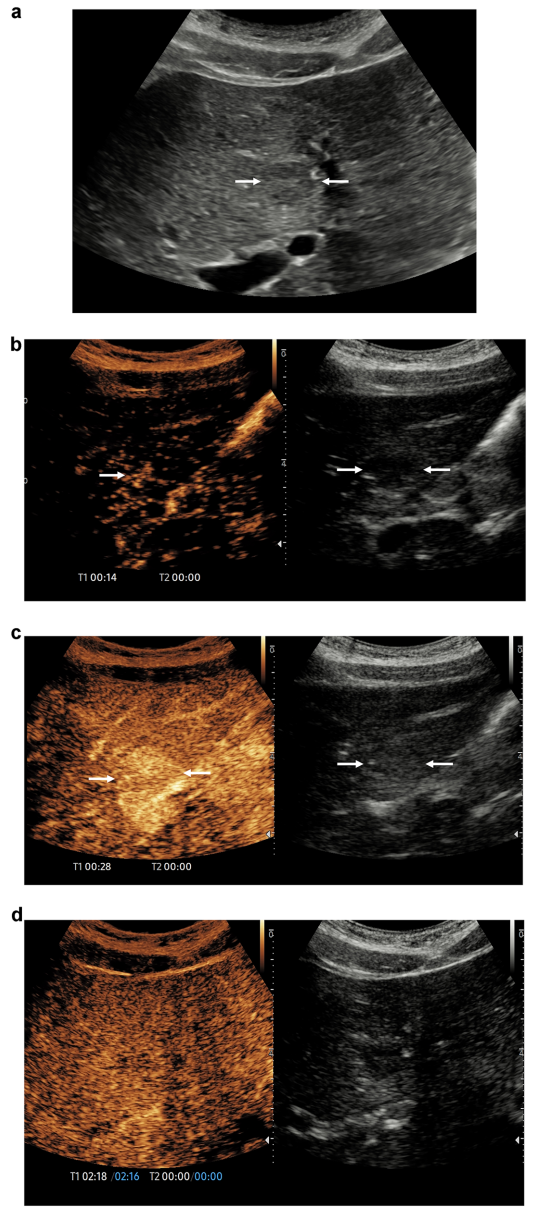

腹部创伤:辐射free的血管侦探

CEUS对实质器官损伤的敏感性达93.3%(CT为95.6%),39岁摩托车事故患者脾脏假性动脉瘤在CEUS下无所遁形